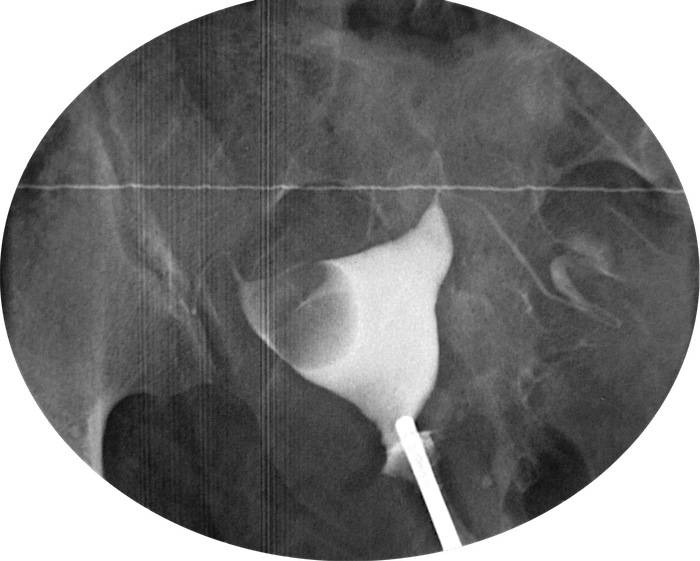

Гистеросальпингография: описание и фотографии